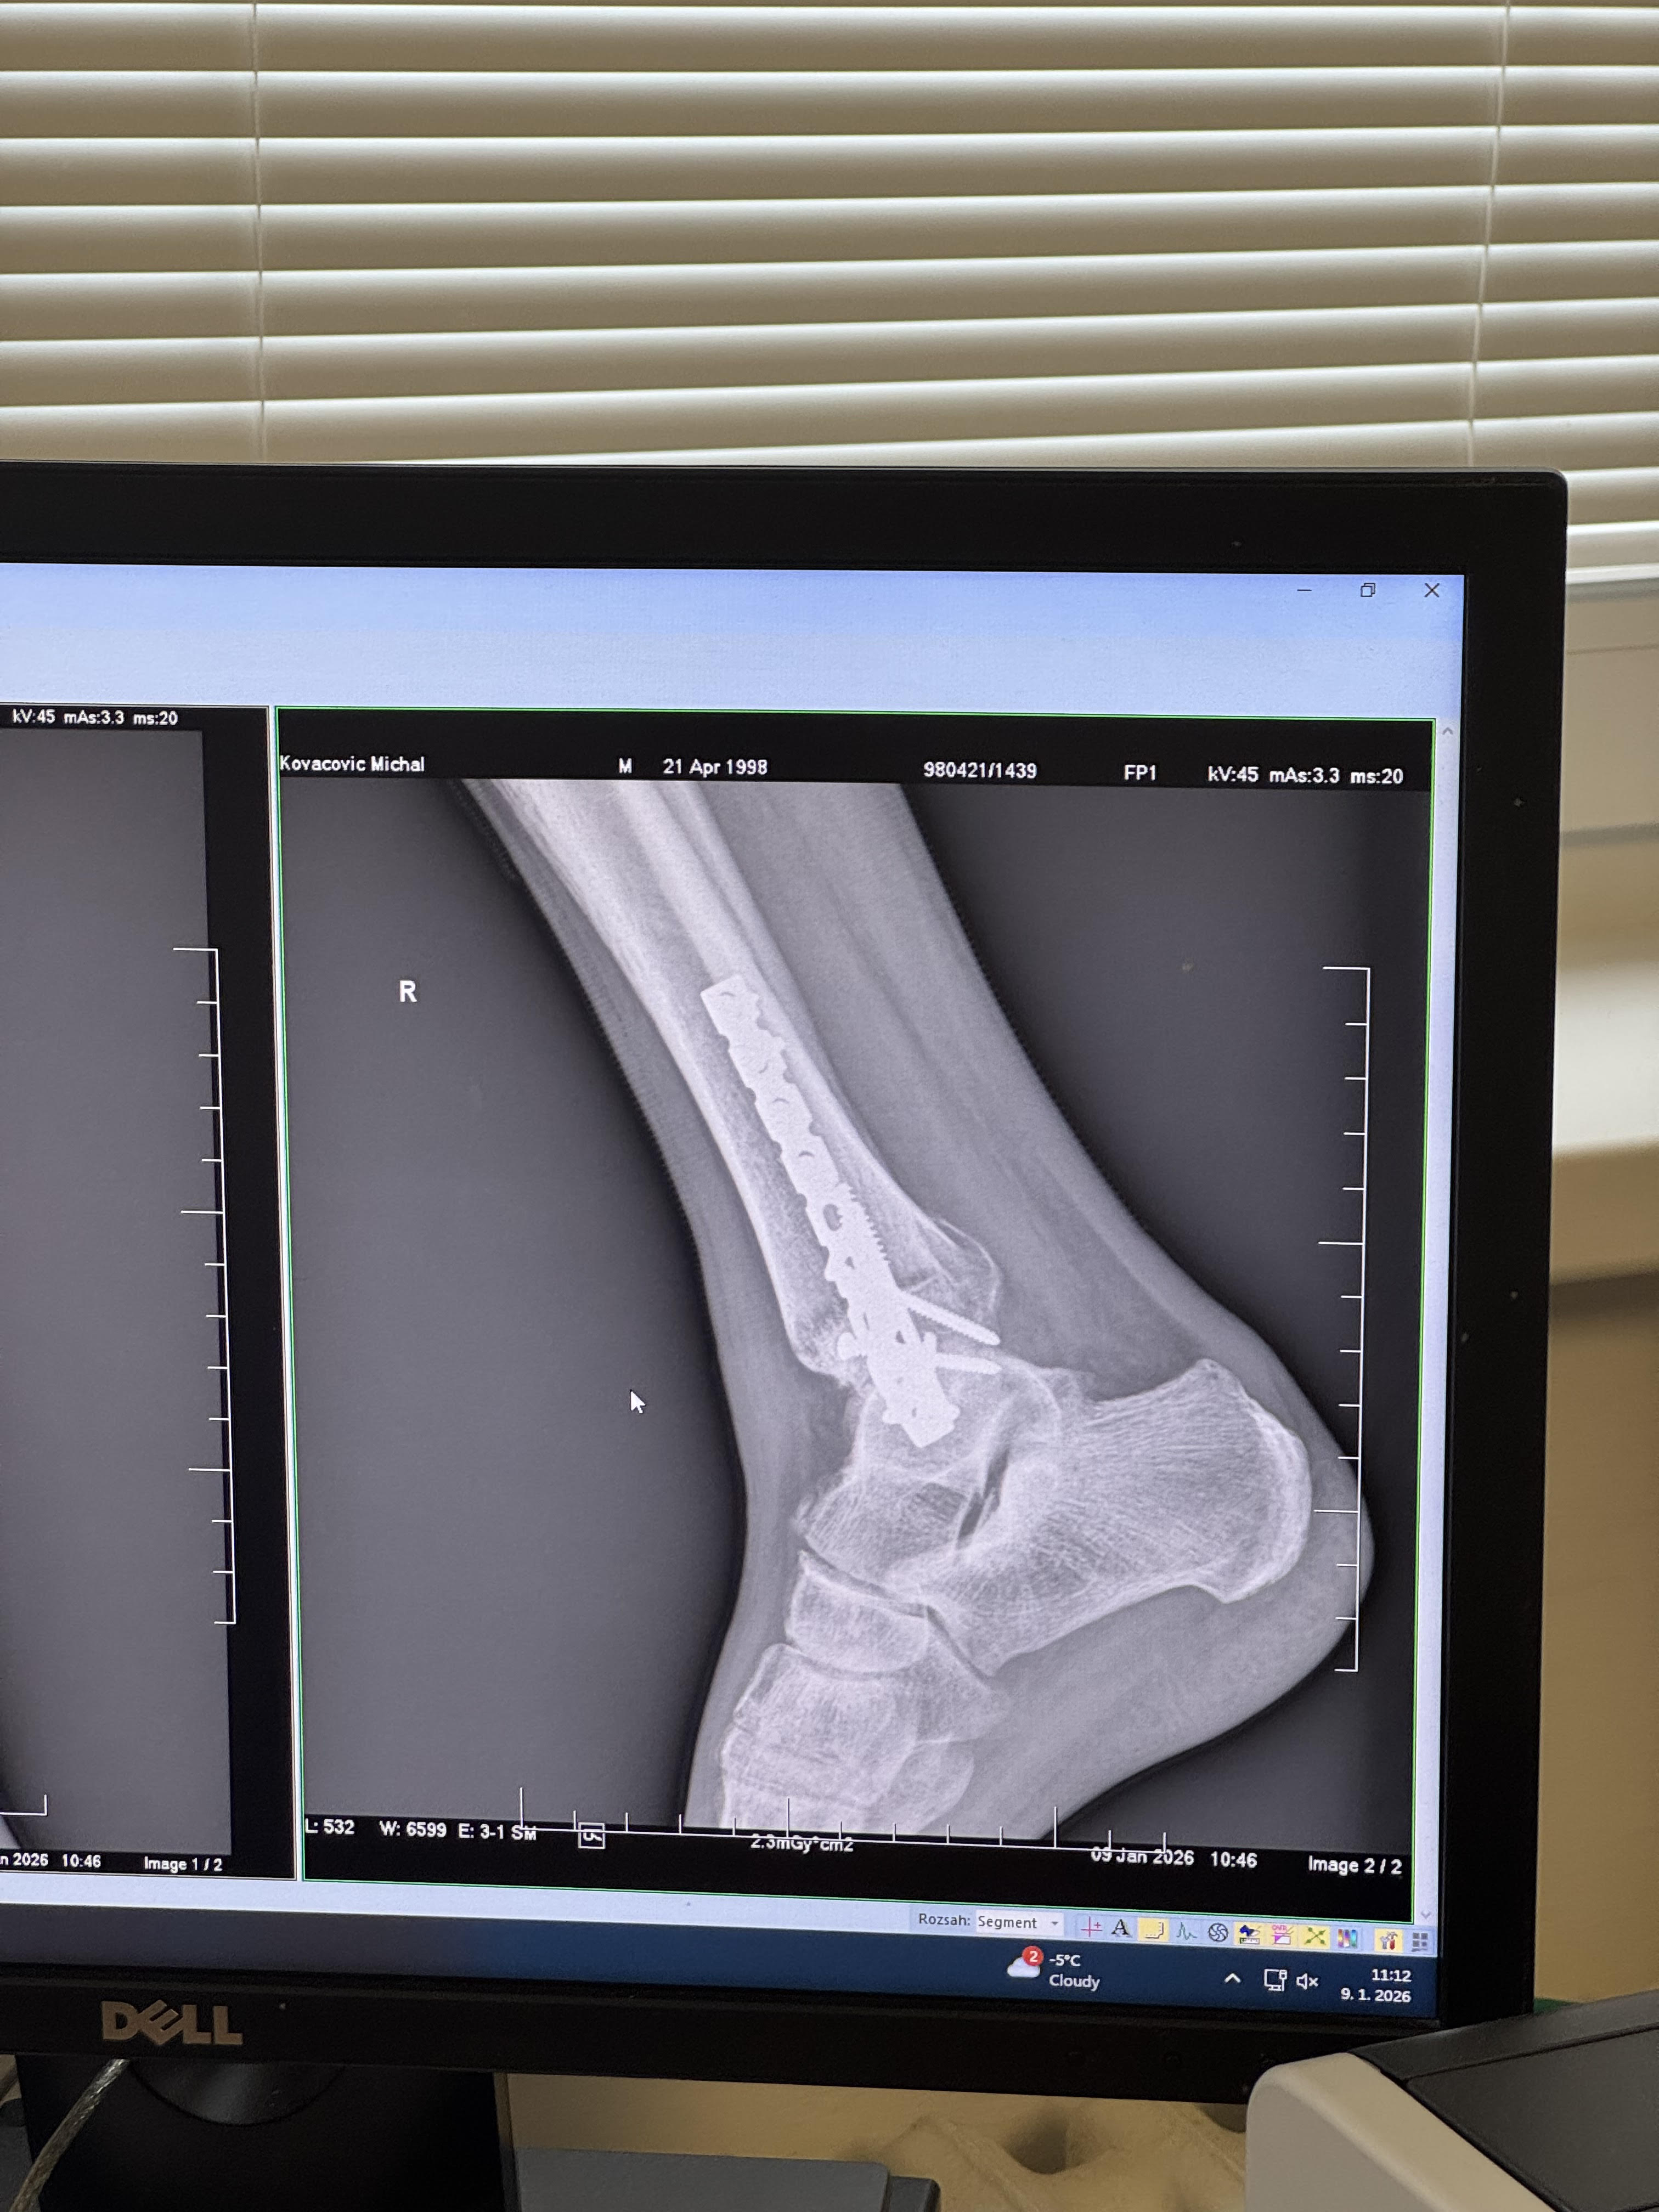

Čau čau makeris, život už docela ide po tom zimnom spánku, čo si si neplánovane doprial, hahah. Hej no, nepríjemná záležitosť, ale tak čo už, aj toto je súčasť hry, ktorú hráme. V novembri na poslednom repre tripe v Mníchove sa mi hneď prvý deň podarilo si prisadnúť nohu, čo znamenalo zlomené všetky tri kosti členku a celkom komplikovanú operáciu, ehhhh… Našťastie mám okolo seba veľa šikovných ľudí, ktorí mi pomáhajú dostať sa ešte do lepšej formy, ako som bol predtým!

Aj toto je bmx life - zlomený členok